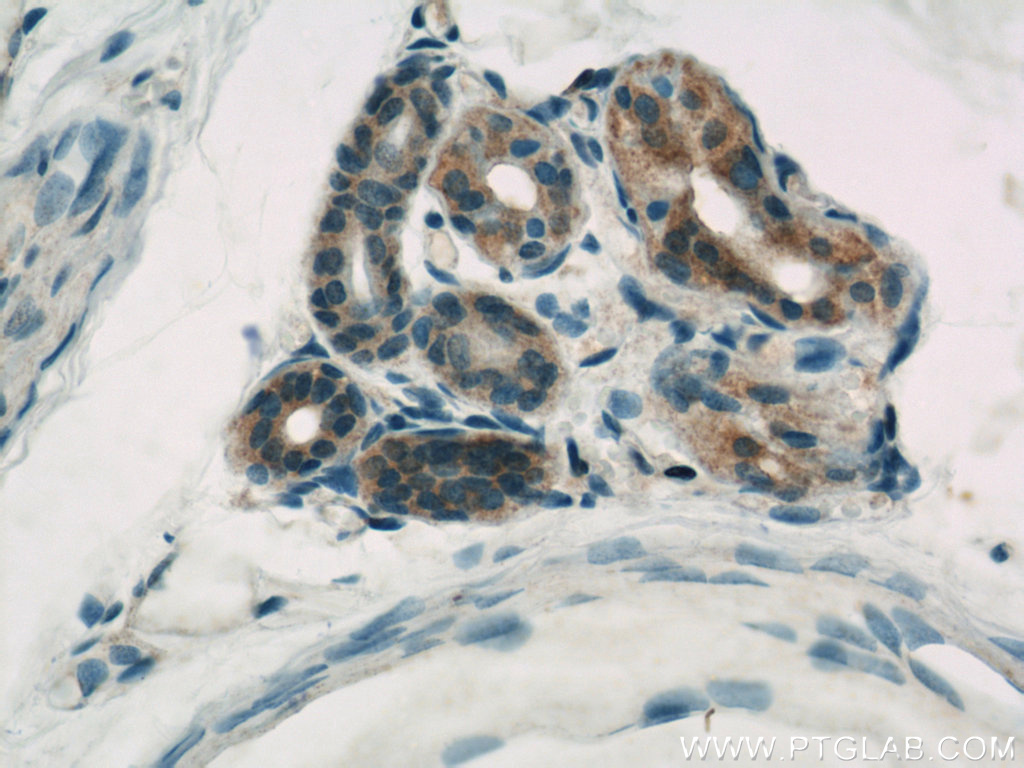

| Positive IHC detected in | human lung cancer tissue, human prostate cancer tissue, human skin tissue Note: suggested antigen retrieval with TE buffer pH 9.0; (*) Alternatively, antigen retrieval may be performed with citrate buffer pH 6.0 |

| Immunohistochemistry (IHC) | IHC : 1:50-1:500 |